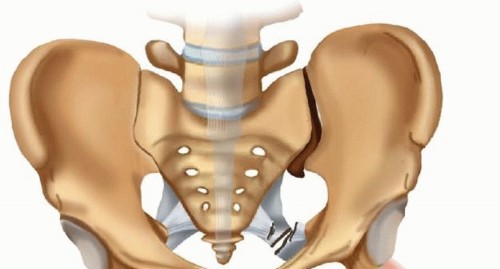

The pubic symphysis comprises a fibrocartilaginous disc between the bodies of the two pubic bones. A diastasis of the pubic symphysis indicates a disruption of the pelvic ring and an unstable pelvis. The symphysis is disrupted in anterior-posterior compression (APC) injuries as classified by Young and Burgess and occasionally in lateral compression fractures. ## ANATOMY The symphysis is an amphiarthrodial joint, consisting of a fibrocartilaginous disc, and stabilized by the superior and inferior arcuate ligaments ( FIG 1A). The corona mortis is a vessel that represents the anastomosis between the obturator artery and the external iliac artery. It is located about 6 cm laterally on either side of the symphysis ( FIG 1B).15 Lateral to the symphysis on the superior rami is the pubic tubercle, a prominence representing the attachment of the inguinal ligament. This bony landmark must be accounted for when contouring a plate that is going to span the symphysis. Anatomic variation exists between the sexes, with females having a wider and more rounded pelvis, making their anterior pelvic ring more concave than males ( FIG 2). The pelvic arch formed by the convergence of the inferior rami tends to be more rounded in females because their pubic bodies are shallower than males.

### FIG 1 • A. View of the anterior pelvis demonstrating the fibrocartilaginous disc between the pubic bodies, the superior and inferior arcuate ligaments, and the relationship between the symphysis and the pubic tubercles. B. The corona mortis is demonstrated on the inside of the superior pubic rami about 6 cm from the symphysis. It represents the anastomosis of the obturator artery and the external iliac artery. The arcuate ligaments are the main soft tissue stabilizers of the anterior pelvis. These ligaments arc both superiorly and inferiorly and are firmly attached to the pubic rami. The sacrospinous and sacrotuberous ligaments play an important role in the stability of pelvic fractures. These ligaments connect the sacrum to the ilium via the ischial spine and the ischial tuberosity. The sacrospinous ligament resists the rotational forces of the hemipelvis, and the sacrotu berous ligament prevents rotation as

well as translation of the hemipelvis. 13